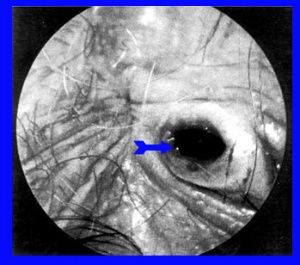

טחורים חיצוניים אינם דורשים טיפול. אם הם גדולים מאוד, צוברים לכלוך ומקשים על הגיינה מקומית, יש לשקול לכורתם. טחורים פקקתיים (תמונה 15.7) מכאיבים אפשר לפתוח בהרדמה מקומית, להוציא את הקריש ולהקל על הכאב (Thrombectomy of thrombosed external hemorrhoid). תמונה 16.7 מראה את המקום לאחר הוצאת הקריש. בחולים המופיעים עם פקקת כזו לאחר 84 שעות מתחילת התסמינים יש לטפל שמרנית ואין טעם לתרומבקטומיה.